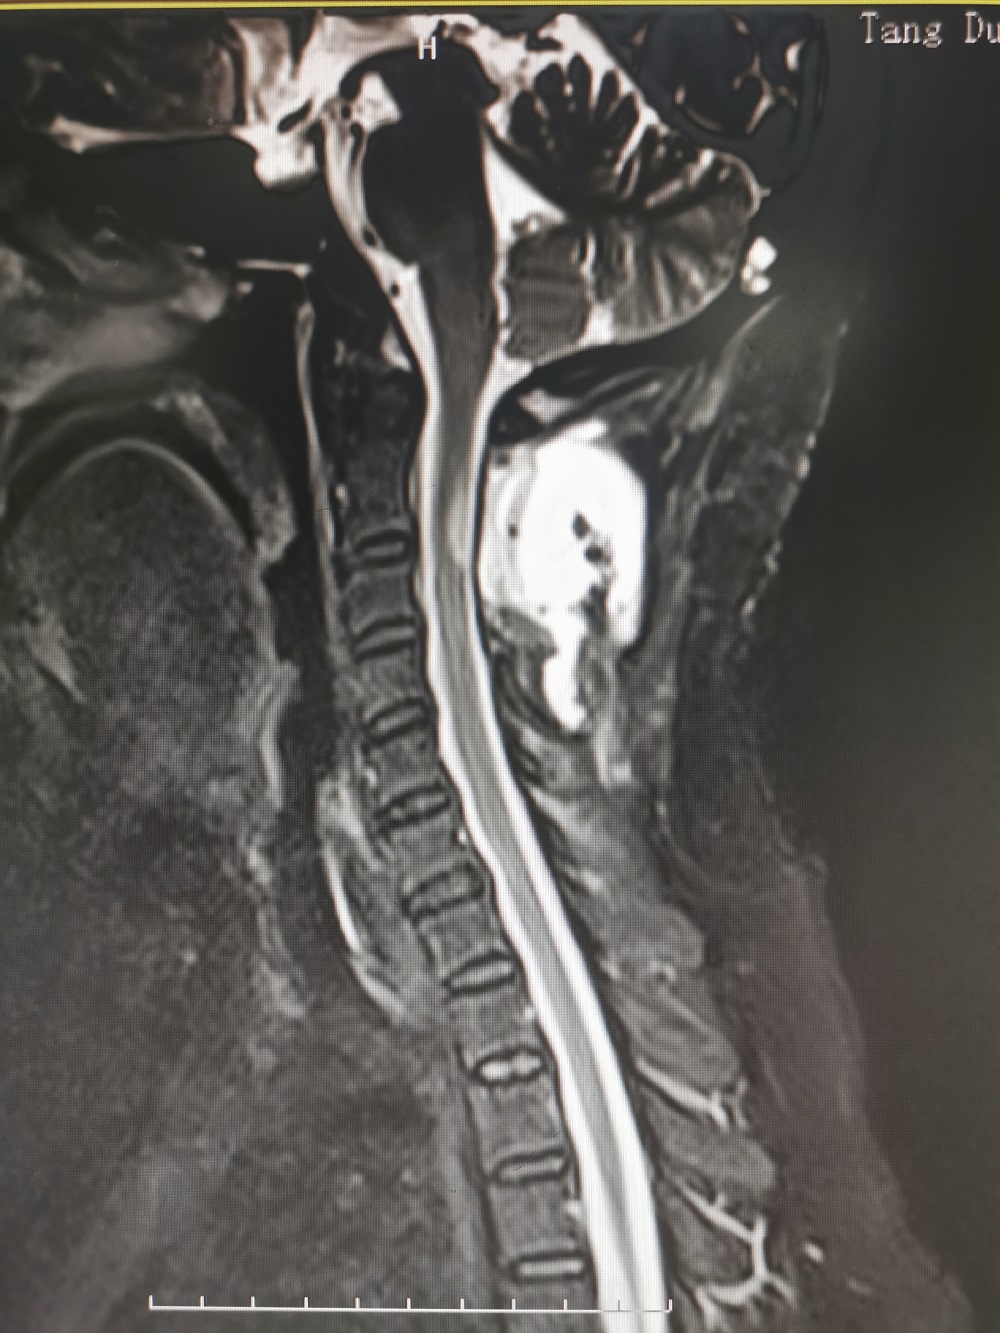

结果颈椎核磁共振检查发现,马女士颈2椎管内肿瘤(术后病理检查为脊膜瘤),颈5-6、6-7出现颈椎间盘突出,并且还有颈椎骨质增生。

术前影像学检查

鉴于目前马女士症状明显并且有加重迹象,从各项检查来看,椎管内肿瘤位于高颈段,脊髓受压严重,而且还伴有颈椎间盘突出和颈椎骨质增生,病情较为复杂,如果不积极治疗后果不堪设想。综合评定分析后,廖博主任建议马女士应该尽快手术治疗。